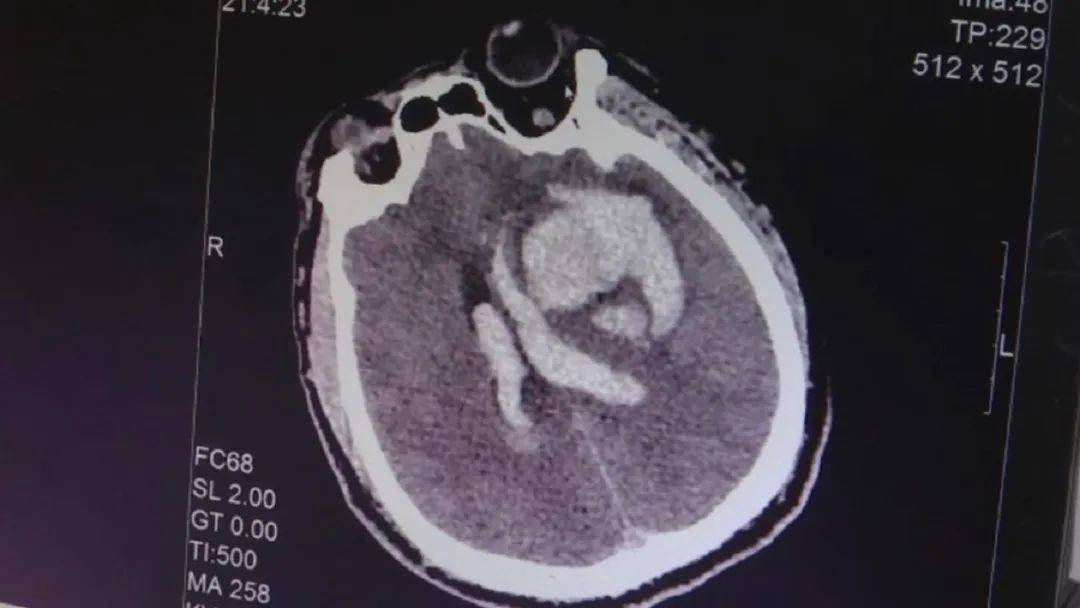

云南大学附属医院急诊内科医生 胡锐:“脑出血有大量脑出血 , 这些都是 , 这一块都是脑出血 , 出血量有可能继续增加 , 脑中线都已经偏了 。 ”

云南大学附属医院急诊内科医生 胡锐:“CT结果确实也证实了我们最初的想法 , 患者发生了大量的脑出血 , 我们估算了一下出血量大概有90毫升 , 化验结果发现患者还出现了横纹肌溶解 , 我们推测患者发生了昏迷之后长期处于一种姿势 , 肌肉长时间在压迫状态下(没有血液供应) , 形成肢端的坏死 。 ”